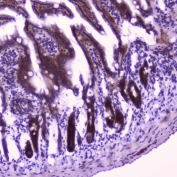

IHC testing of FFPE mouse small intestine tissue with FLIP antibody at 2ug/ml. HIER: boil tissue sections in pH6, 10mM citrate buffer, for 10-20 min followed by cooling at RT for 20 min.

IHC testing of FFPE rat small intestine tissue with FLIP antibody at 2ug/ml. HIER: boil tissue sections in pH6, 10mM citrate buffer, for 10-20 min followed by cooling at RT for 20 min.